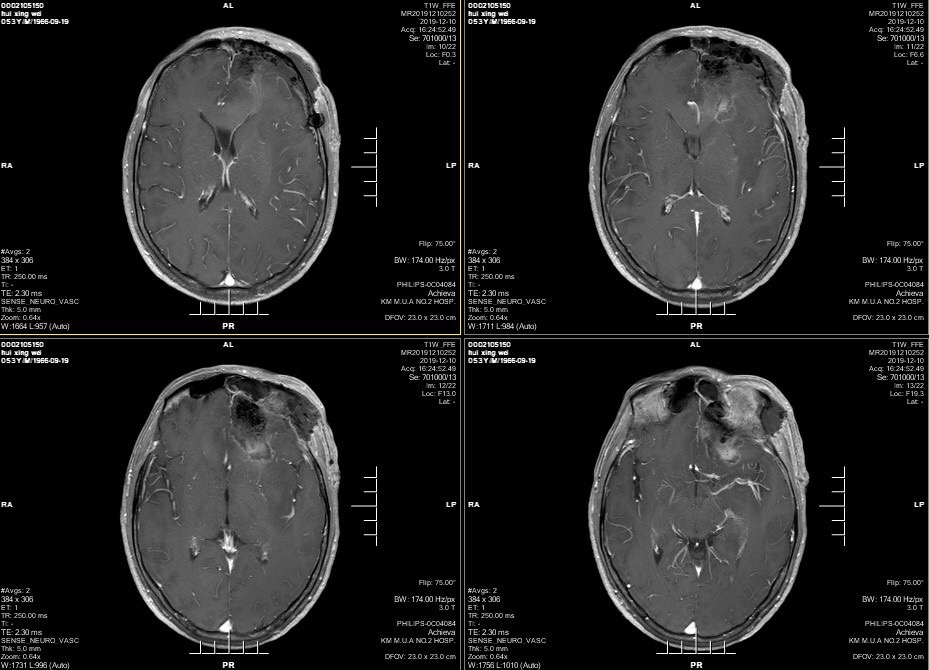

男性患者,53岁,主诉:反复头痛伴恶心一周,突发意识丧失一次。入院查体:神经体统无阳性体征。入院头颅MRI:左额叶胼胝体区囊实性占位,不均匀强化,考虑高级别胶质瘤;长程视频脑电监测提示左侧中央区、顶区、后颞区见中等量低-中-高波幅痫样放电。术前诊断:1.左额叶胼胝体区占位病变;2.继发性癫痫,入院给予降颅压及抗癫痫处理,积极完善术前准备后于2019年12月3日全麻下完成手术,术中行B超引导下切除肿瘤。术后患者无肢体功能及语言功能障碍,复查头颅核磁肿瘤全切,一周后出院开始放化疗治疗。

双侧大脑前动脉受肿瘤推挤。

增强后不均匀强化。